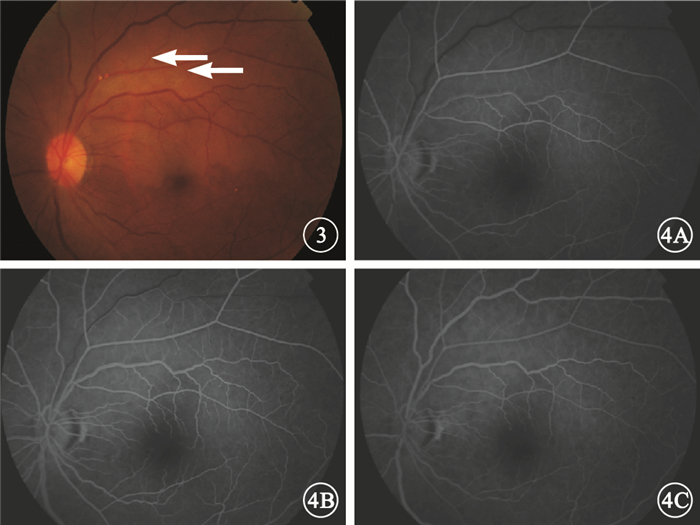

圖2

患者頸動脈超聲多普勒檢查像。2A.左側,頸內動脈粥樣硬化斑,內未探及明顯血流信號;2B.右側,頸內動脈粥樣硬化斑伴狹窄,狹窄程度約70%

圖2

患者頸動脈超聲多普勒檢查像。2A.左側,頸內動脈粥樣硬化斑,內未探及明顯血流信號;2B.右側,頸內動脈粥樣硬化斑伴狹窄,狹窄程度約70%

圖2

患者頸動脈超聲多普勒檢查像。2A.左側,頸內動脈粥樣硬化斑,內未探及明顯血流信號;2B.右側,頸內動脈粥樣硬化斑伴狹窄,狹窄程度約70%

圖2

患者頸動脈超聲多普勒檢查像。2A.左側,頸內動脈粥樣硬化斑,內未探及明顯血流信號;2B.右側,頸內動脈粥樣硬化斑伴狹窄,狹窄程度約70%